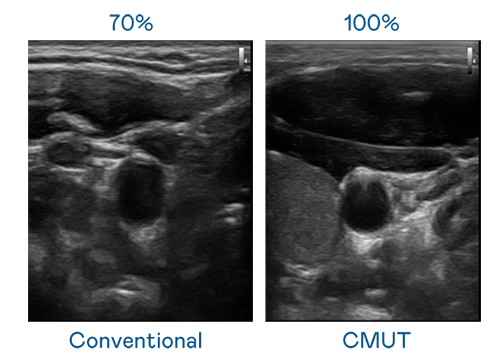

CMUT 技术是一种用电容式微机电元件来产生超音波讯号的技术。与传统 PZT 压电式技术相比,CMUT 频宽增加 30%,更宽频的超音波讯号让影像解析度大幅提升,是实现高影像品质医疗超音波扫描、促进精准医疗发展的关键技术。

大频宽带来超清晰影像

超音波影像的解析度高低,首先取决于探头能发出的讯号频宽。yl23411永利 CMUT 可提供高清晰的超音波讯号,提供高频宽、高灵敏度、影像纹理细节更高的超音波影像,协助医护人员缩短影像判读时间及利用精准的医疗影像进行诊断。